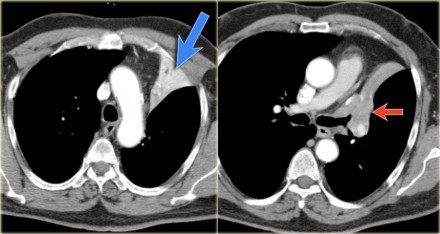

肺不张ct经典图片

肺不张ct

肺不张ct图片

肺不张影像

肺不张ct表现

肺不张影像学